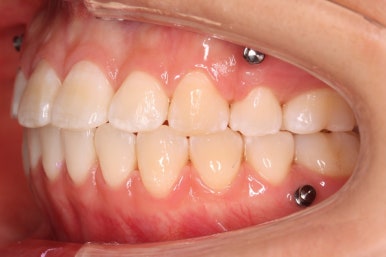

다시 이번 환자분으로 돌아가, 입 안모습을 보시겠습니다.

부산무턱교정 키다리아저씨치과에서 처음 내원하셨을 당시의 입 안의 모습입니다.

아래턱이 작아서 상대적으로 윗니들이 많이 돌출되었고, 뻐드러져 있습니다. 윗니들이 배열되어 있는 형태도 V자에 가깝게 입천장이 좁은 양상입니다.

윗니는 발치를 했고, 잇몸뼈에 미니스크류를 식립하여 앞니를 뒤로 당겨넣고 있습니다.

아랫니는 아직 덜 가지런해졌네요.